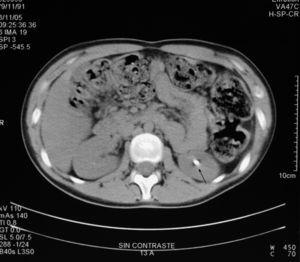

En la ecografía renal, se observaron imágenes con sombra acústica en ambos riñones y en la tomografía computarizada (TC) helicoidal 2 cálculos radioopacos en los grupos caliciales superior e inferior del riñón derecho, y otro más situado en el grupo calicial inferior del riñón izquierdo, excluyéndose la dilatación de la vía urinaria y la presencia de cálculos ureterales (figs. 1 y 2).

Figura 1. Ecografía renal: cálculo en grupo calicial inferior del riñón izquierdo (flecha color blanco).